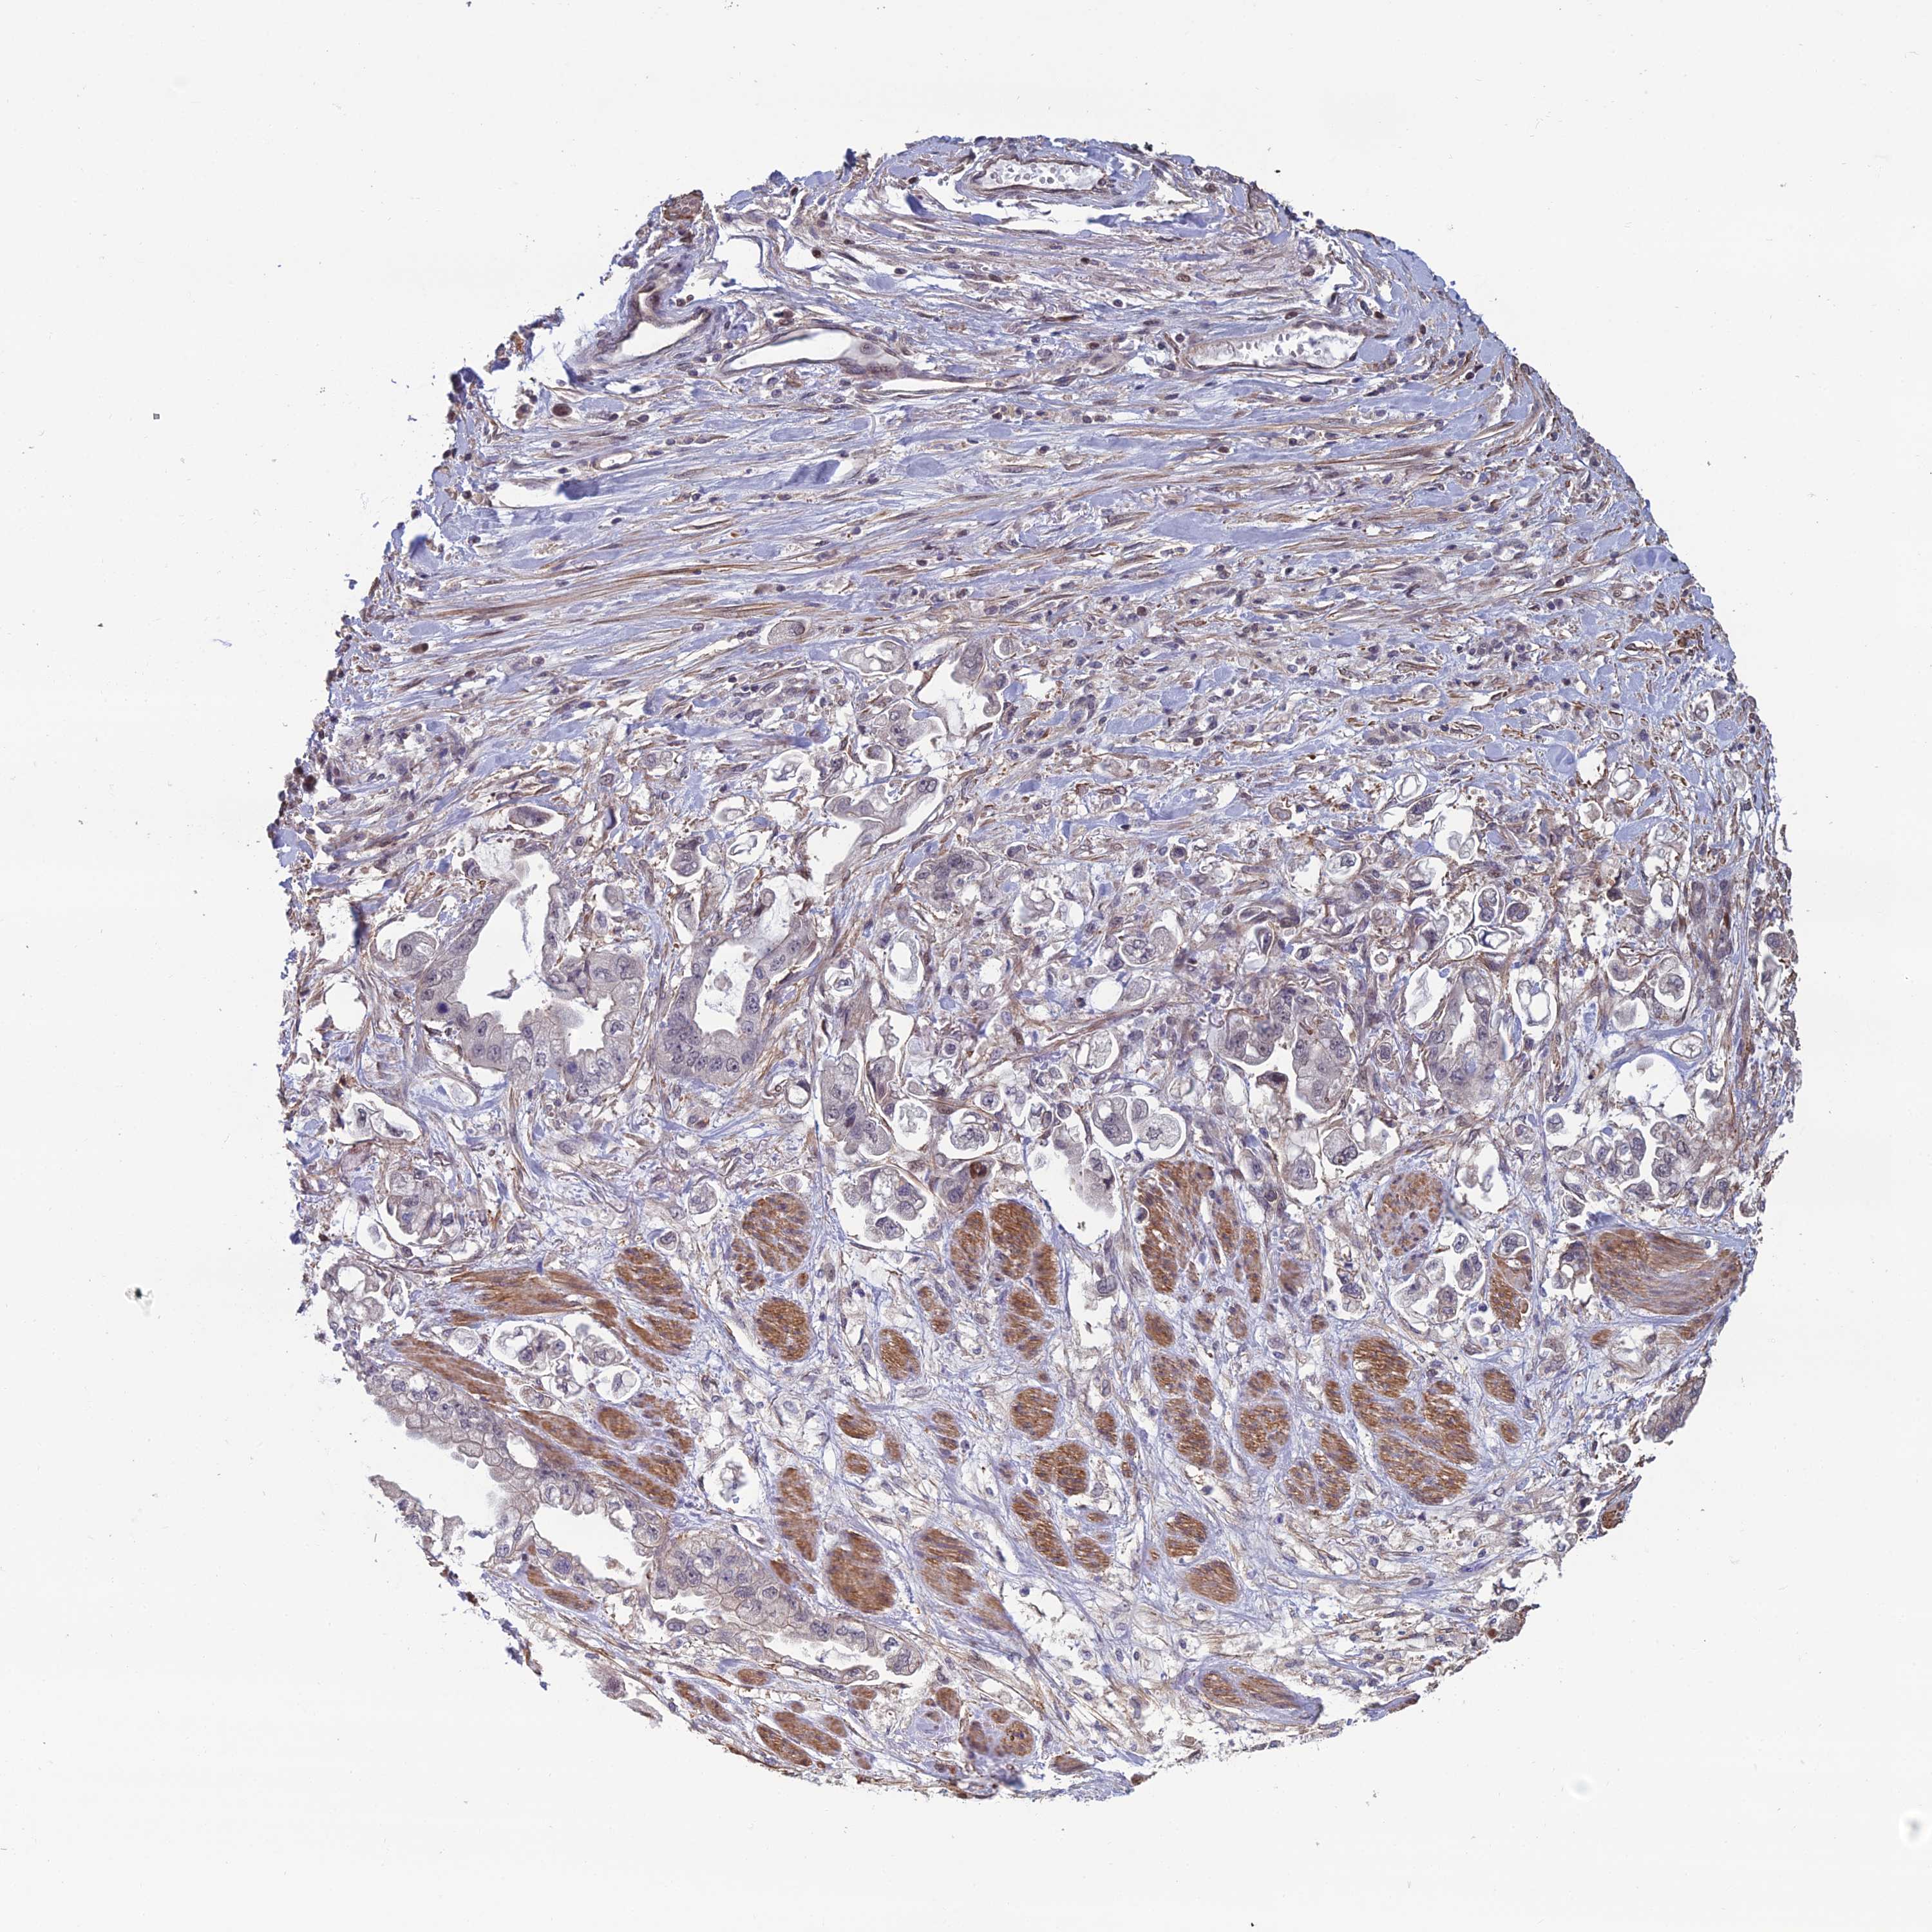

STOMACH CANCER - Protein expressioni

A mouse-over function shows sample information and annotation data. Click on an image to view it in a full screen mode. Samples can be filtered based on level of antibody staining by selecting one or several of the following categories: high, medium, low and not detected. The assay and annotation is described here.

Note that samples used for immunohistochemistry by the Human Protein Atlas do not correspond to samples in the TCGA dataset.

Antibody stainingi

Antibody staining in the annotated cell types in the current human tissue is reported as not detected, low, medium, or high, based on conventional immunohistochemistry profiling in selected tissues. This score is based on the combination of the staining intensity and fraction of stained cells.

Each image is clickable and will lead to virtual microscopy that enables deeper exploration of all samples and also displays staining intensity scores, fraction scores and subcellular localization as well as patient and tissue information for each sample.

Antibody HPA043812

Staining

High

Medium

Low

Not detected

Intensity

Strong

Moderate

Weak

Negative

Quantity

>75%

75%-25%

<25%

None

Location

Nuclear

Cytoplasmic/membranous

Cytoplasmic/membranous,nuclear

Adenocarcinoma, NOS